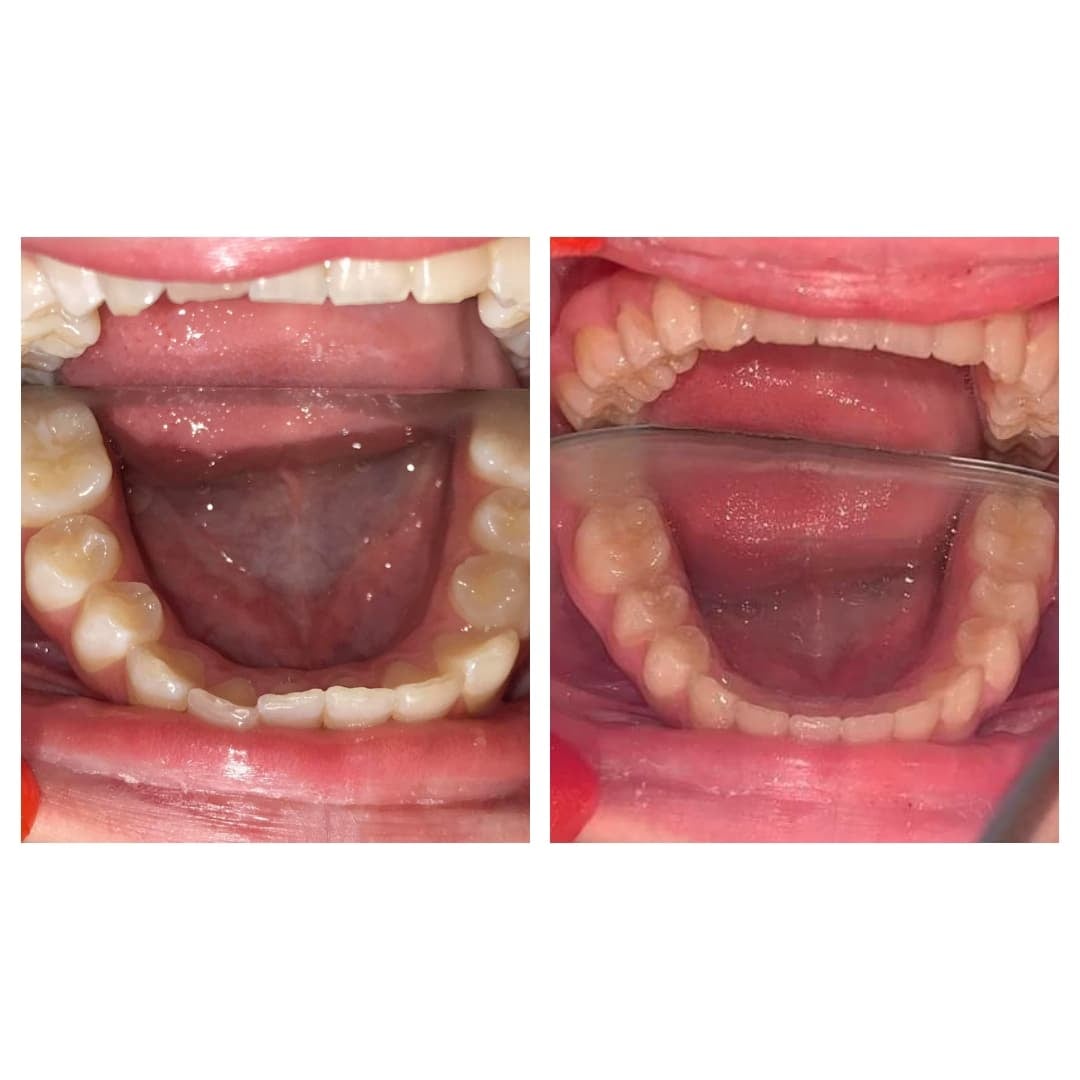

Weronika nosiła 31 nakładek Invisalign® w pierwszej serii, a następnie 18 nakładek w drugiej serii. Zmieniała nakładki co 7 dni. Leczenie trwało niecały rok.

Nasza pacjentka zapoznała się ze wszystkimi wadami i zaletami Invisalign®, rozważyła również inne metody leczenia ortodontycznego, m.in. klasyczne druty i zamki.

Rodzice Weroniki oszacowali, że koszty leczenia klasyczną metodą podczas 2-letniego noszenia aparatu na zęby będą porównywalne do kosztów leczenia metodą Invisalign®. Teraz pacjentką kliniki jest Mama Weroniki, która widząc znakomite efekty u Córki postanowiła poprawić swój uśmiech i zgryz.